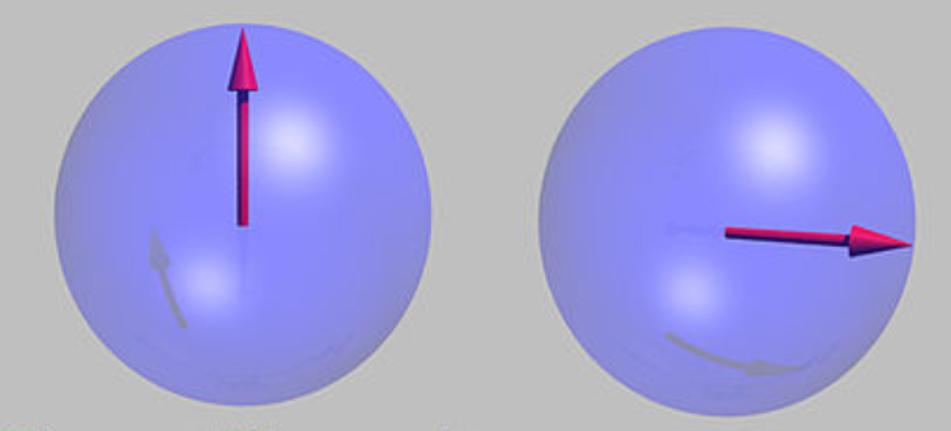

在外磁场作用下,质子自旋磁矩平行或反平行于外磁场

自旋的质子在外磁场下做进动